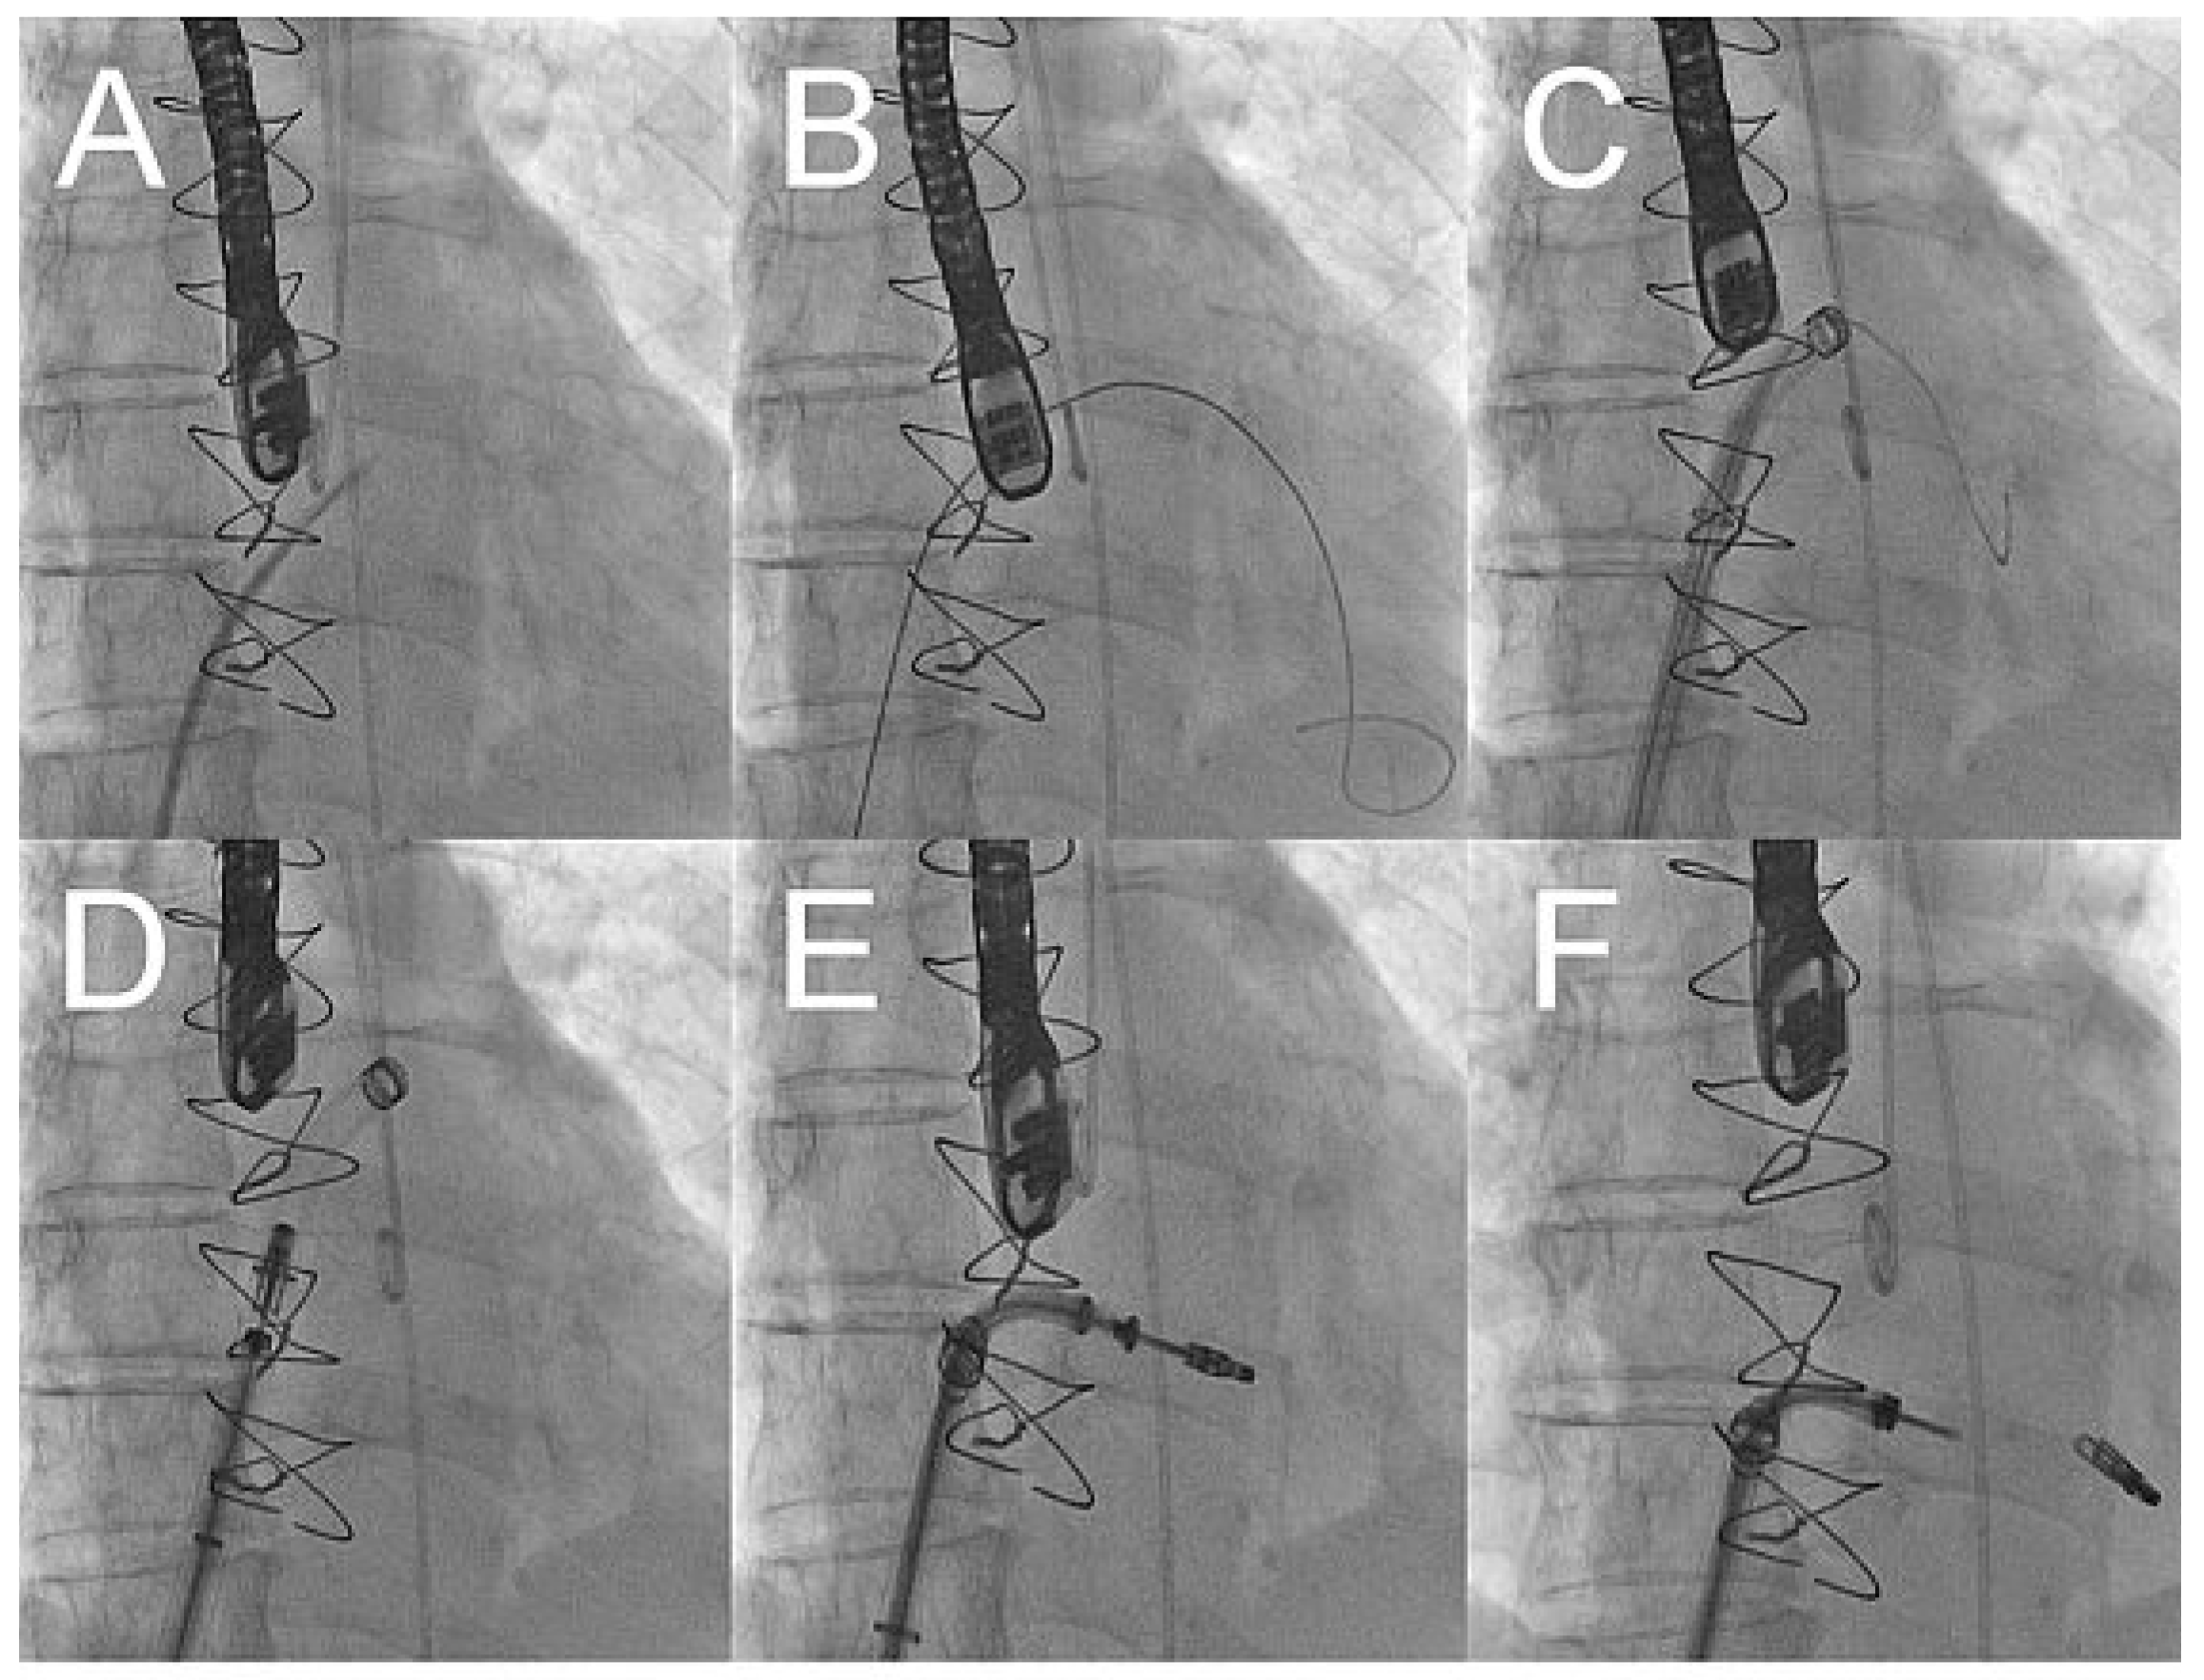

After gaining access through an 8 french sheath via the right femoral vein, transseptal puncture was performed under TEE and fluoroscopic-guidance, and an Amplatz-Super-Stiff® catheter was advanced into the left atrium (fig. 3A–C). Changing to a MitraClip-guide catheter, the clip delivery system was advanced via the left atrium (fig. 3D) into mitral position (fig. 3E). The system allows repositioning of the device under echocardiographic control until optimal placement has been found. This meant, before releasing the Clip (fig. 3F), that it could be repositioned until echocardiographic control showed the correct position of the device with mild residual regurgitation (fig. 4). 3-dimensional echocardiographic reconstruction images allowed the positioning and adjusting of the clip (fig. 5A) and the open and closed mitral valve after MitraClip® placement (fig. 5B and 5C) to be seen. The patient could be extubated in the catheter lab directly after clip implantation. The in-hospital recovery was uneventful and the patient could be discharged home three days after the intervention. During her four-week follow-up, the patient was in excellent health and reported a substantial improvement of her symptoms, reducing her exertional dyspnoea symptoms down to NYHA I–II. Echocardiographic control showed the MitraClip® in an optimal place with a residual mild-moderate regurgitation jet. On the chest x-ray film, the metallic clip can easily be identified (fig. 6).

Figure 3. X-ray pictures showing the procedure of MitraClip® placement.